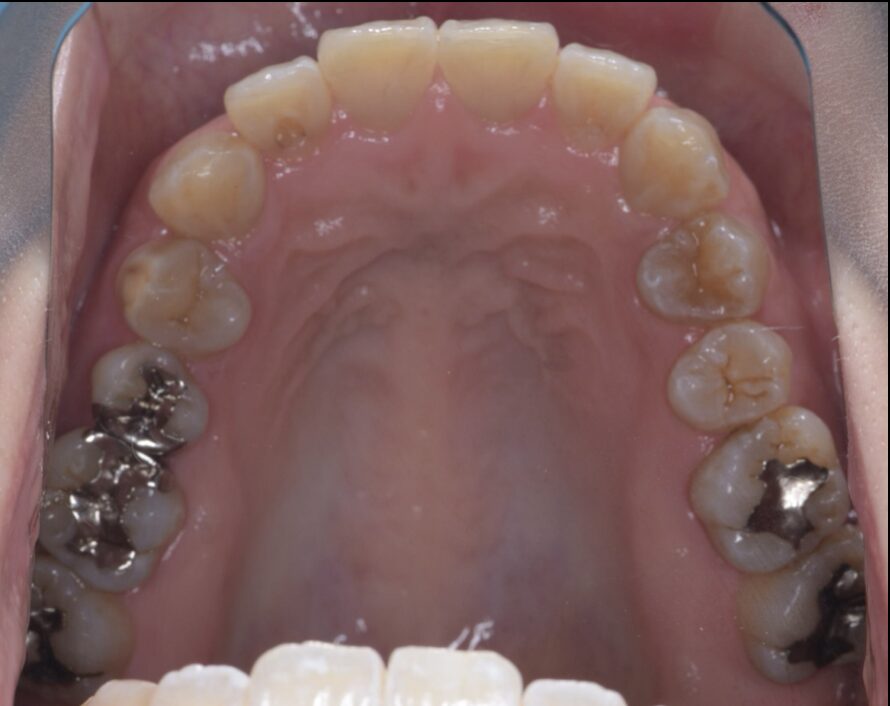

銀歯をセラミックインレー、樹脂での治療(メタルフリー)

Before

| 治療内容 | セラミックインレー |

| 治療期間・治療回数 | 2回 |

| 治療費用 | 143000円(税込) |

| 備考 | 30代 女性 |